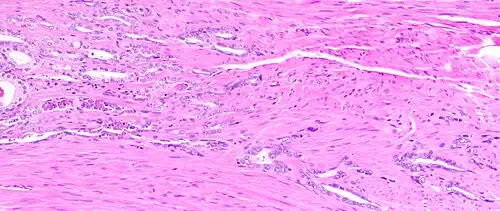

Micrograph showing inflamed prostate (H&E stain) with large amount of darker cells (leukocytes); area without inflammation seen on the left

Prostatitis is inflammation of the prostate gland. It can be caused by infection with bacteria, or other noninfective causes. Inflammation of the prostate can cause painful urination or ejaculation, groin pain, difficulty passing urine, or constitutional symptoms such as fever or tiredness.[28] When inflamed, the prostate becomes enlarged and is tender when touched during digital rectal examination. The bacteria responsible for the infection may be detected by a urine culture.[28]